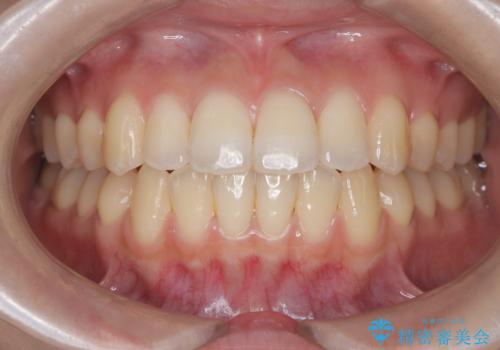

前歯のデコボコと深い咬み合わせを解消